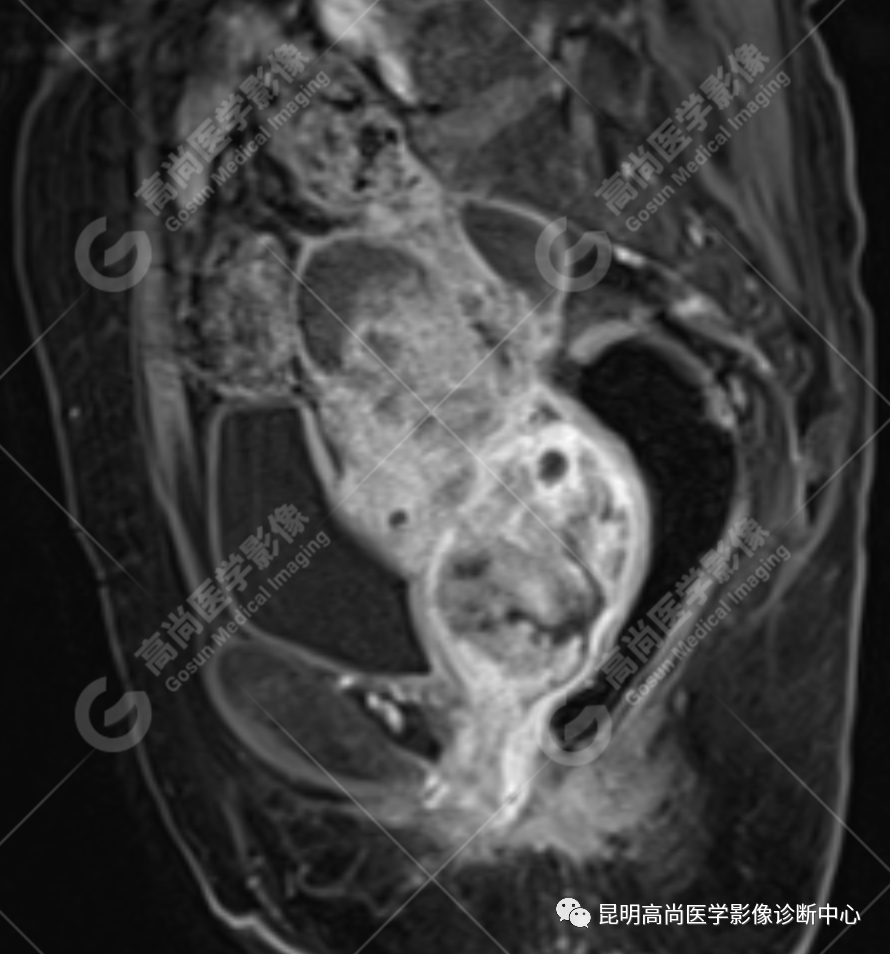

影像诊断

子宫、附件未见显示;下腹部及盆腔内巨大占位,考虑恶性肿瘤,肉瘤可能,阴道及肛管受侵,建议活检。

不规则菜花状或息肉状肿物,子宫内膜正常 T2WI 清晰连续的高信号消失,取而代之是中高、高信号,不均匀混杂信号,信号强度低于内膜正常信号强度,T1WI 上内膜信号增高,子宫肌层明显变薄,未受侵者肌层信号均匀,因肿物组织来源不同,病变信号复杂,以 T2WI 表现为等高混杂信号为主。因病灶较大,可合并囊变坏死及肿瘤出血。

肌层到肿块内的血管流空信号,可提示肿瘤内有血供丰富的肉瘤成分,血管流空信号在子宫内膜癌中未见报道,但在子宫平滑肌瘤、平滑肌肉瘤中可见。